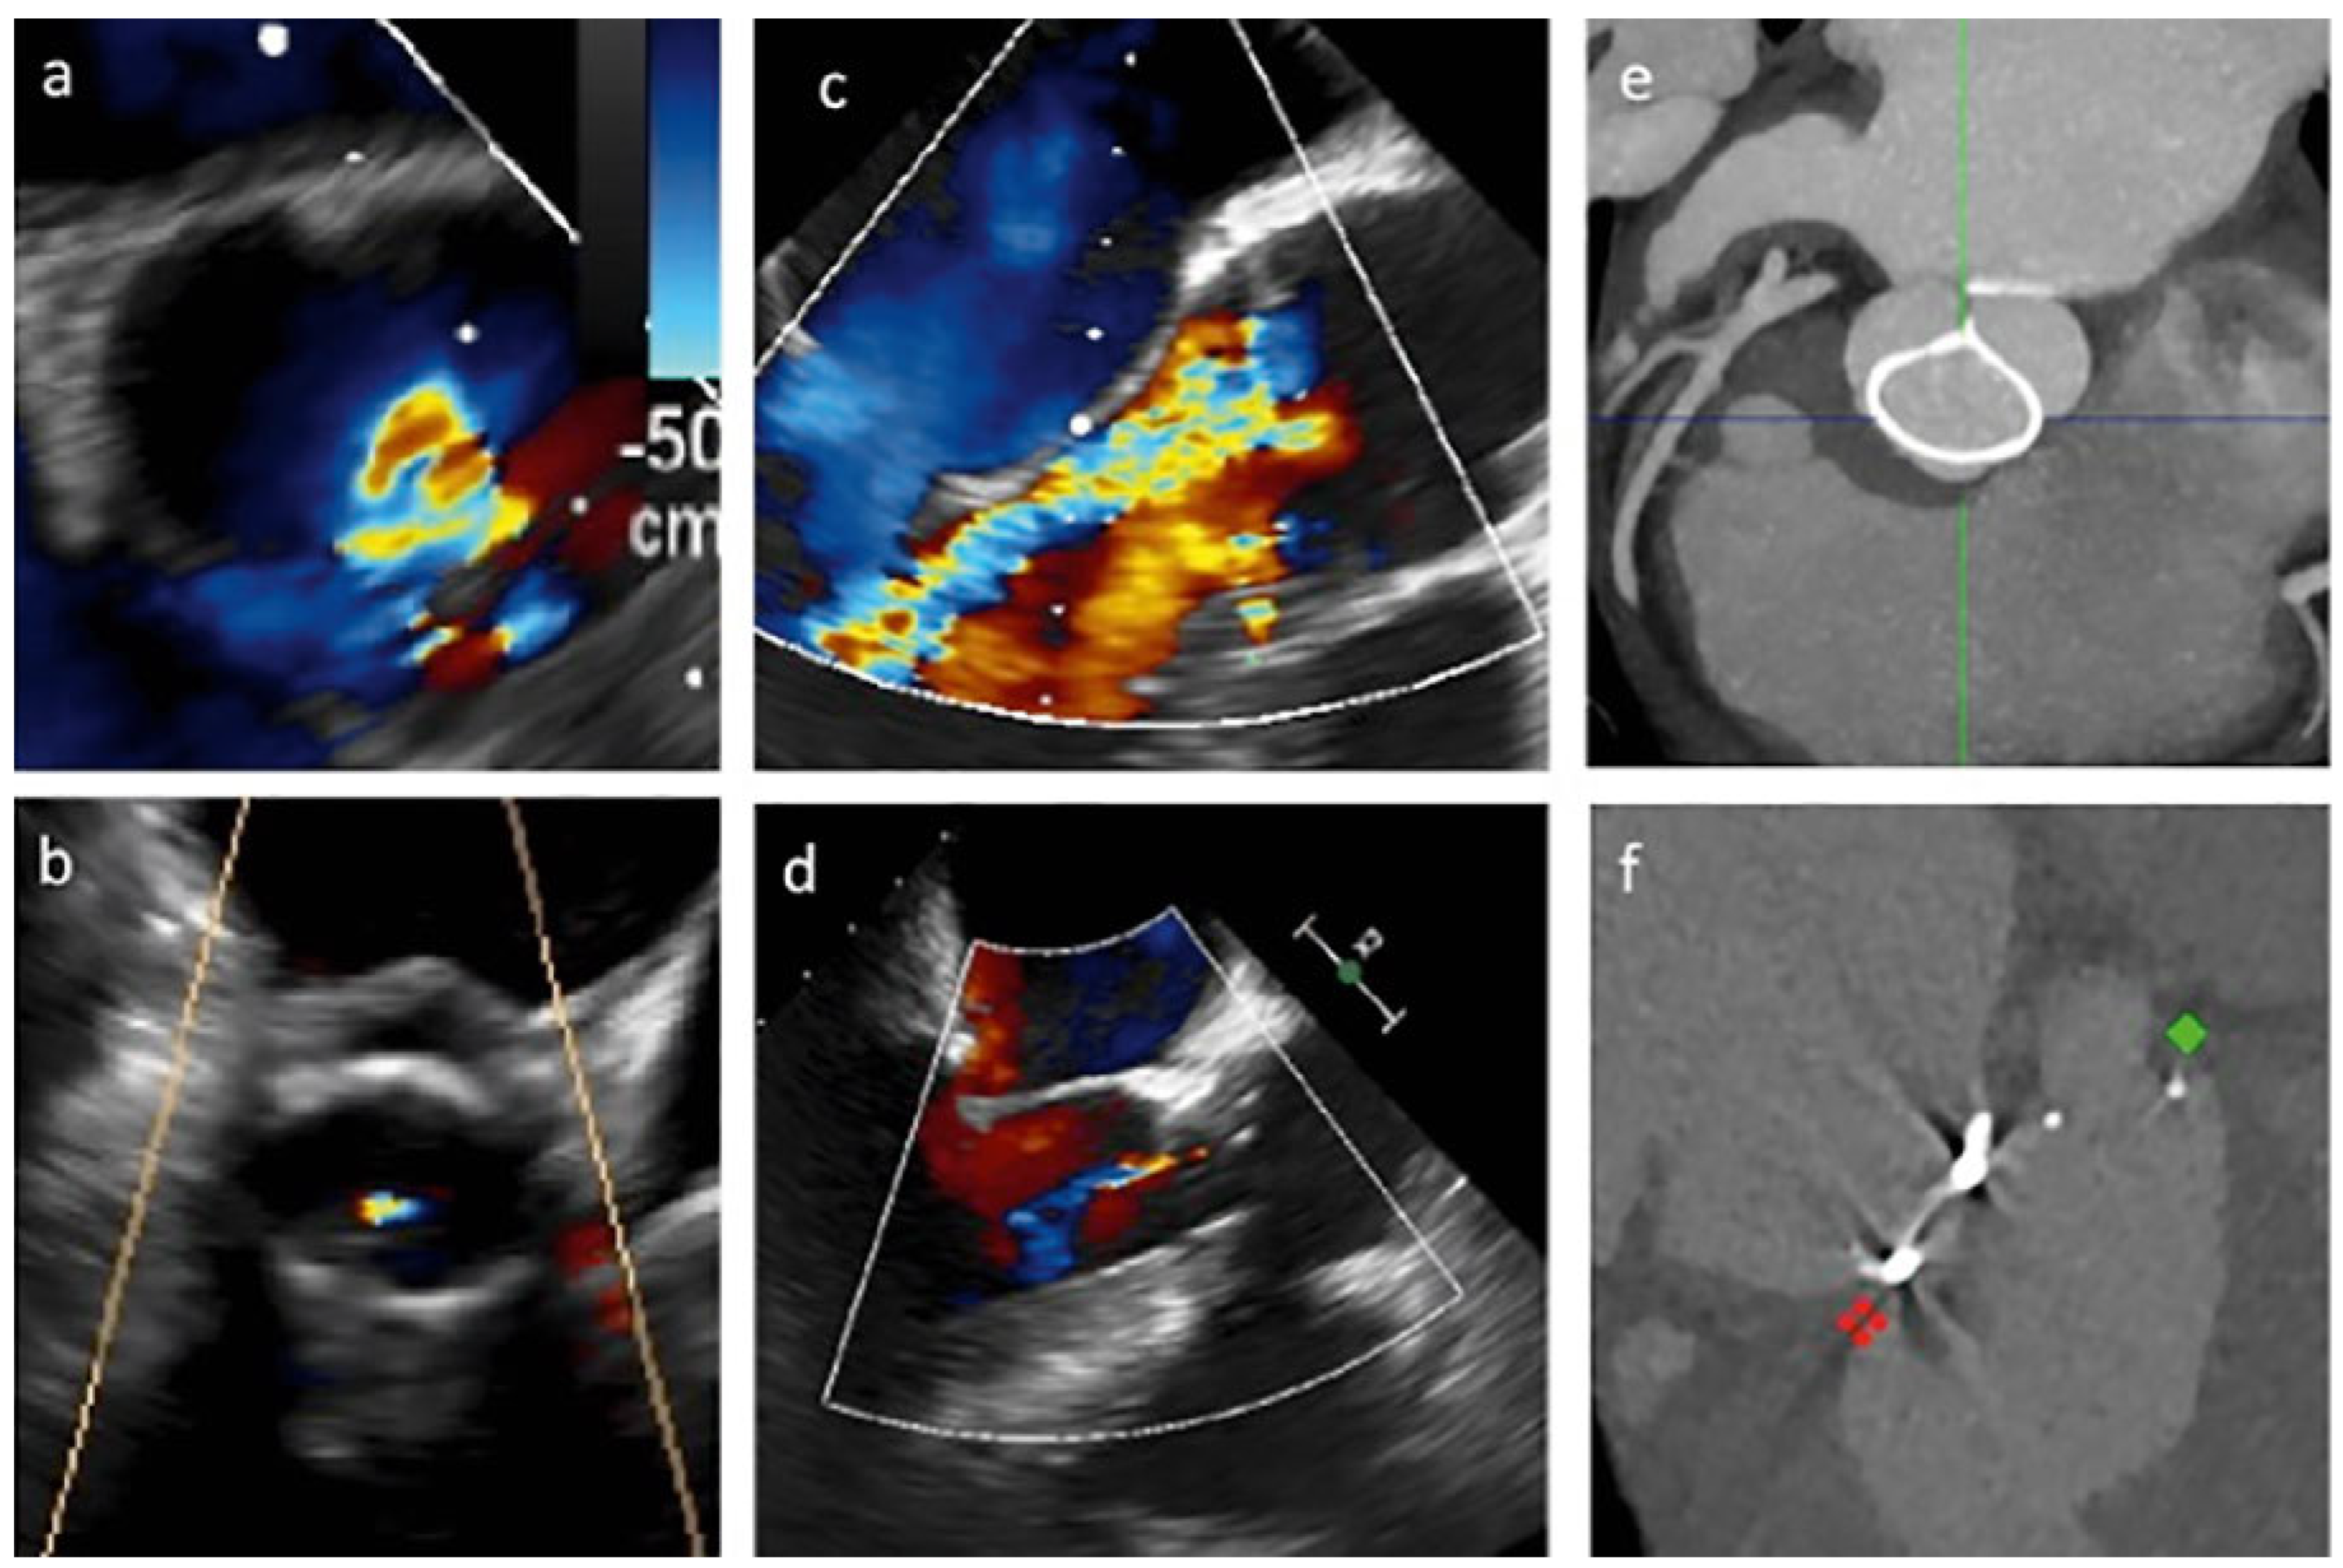

In-hospital survival was 100%. Predischarge echocardiography showed no cases of residual aortic regurgitation classed as more than mild or stenosis. An initial reduction of left ventricle volume was recorded (mean LVEDV 126 ± 36 ml). Echo-analysis before discharge showed a mean regurgitant volume of 13 ± 8 ml/beat. No increased gradients were detected (mean gradient 10 ± 4 mm Hg). Table 2 presents the main echocardiographic results. Postoperative course was event-free, except for one case of transient delirium and two cases of postoperative pericardial effusion in patients with valve sparing operations. No complete atrioventricular block or pacemaker implantation occurred. Mean hospital stay was 8 ± 1 days. Figure 2 presents the results of postoperative imaging evaluations with echocardiography and CT scans.

Figure 2.

Main features of aortic valve repair with HAART ring implantation. (a), (b) Transoesophageal echocardiographic short axis view of the aortic valve before and after repair; (c), (d) long axis view of the aortic valve before and after repair; (e) postoperative CT; (f) postoperative CT showing double ring implantation.